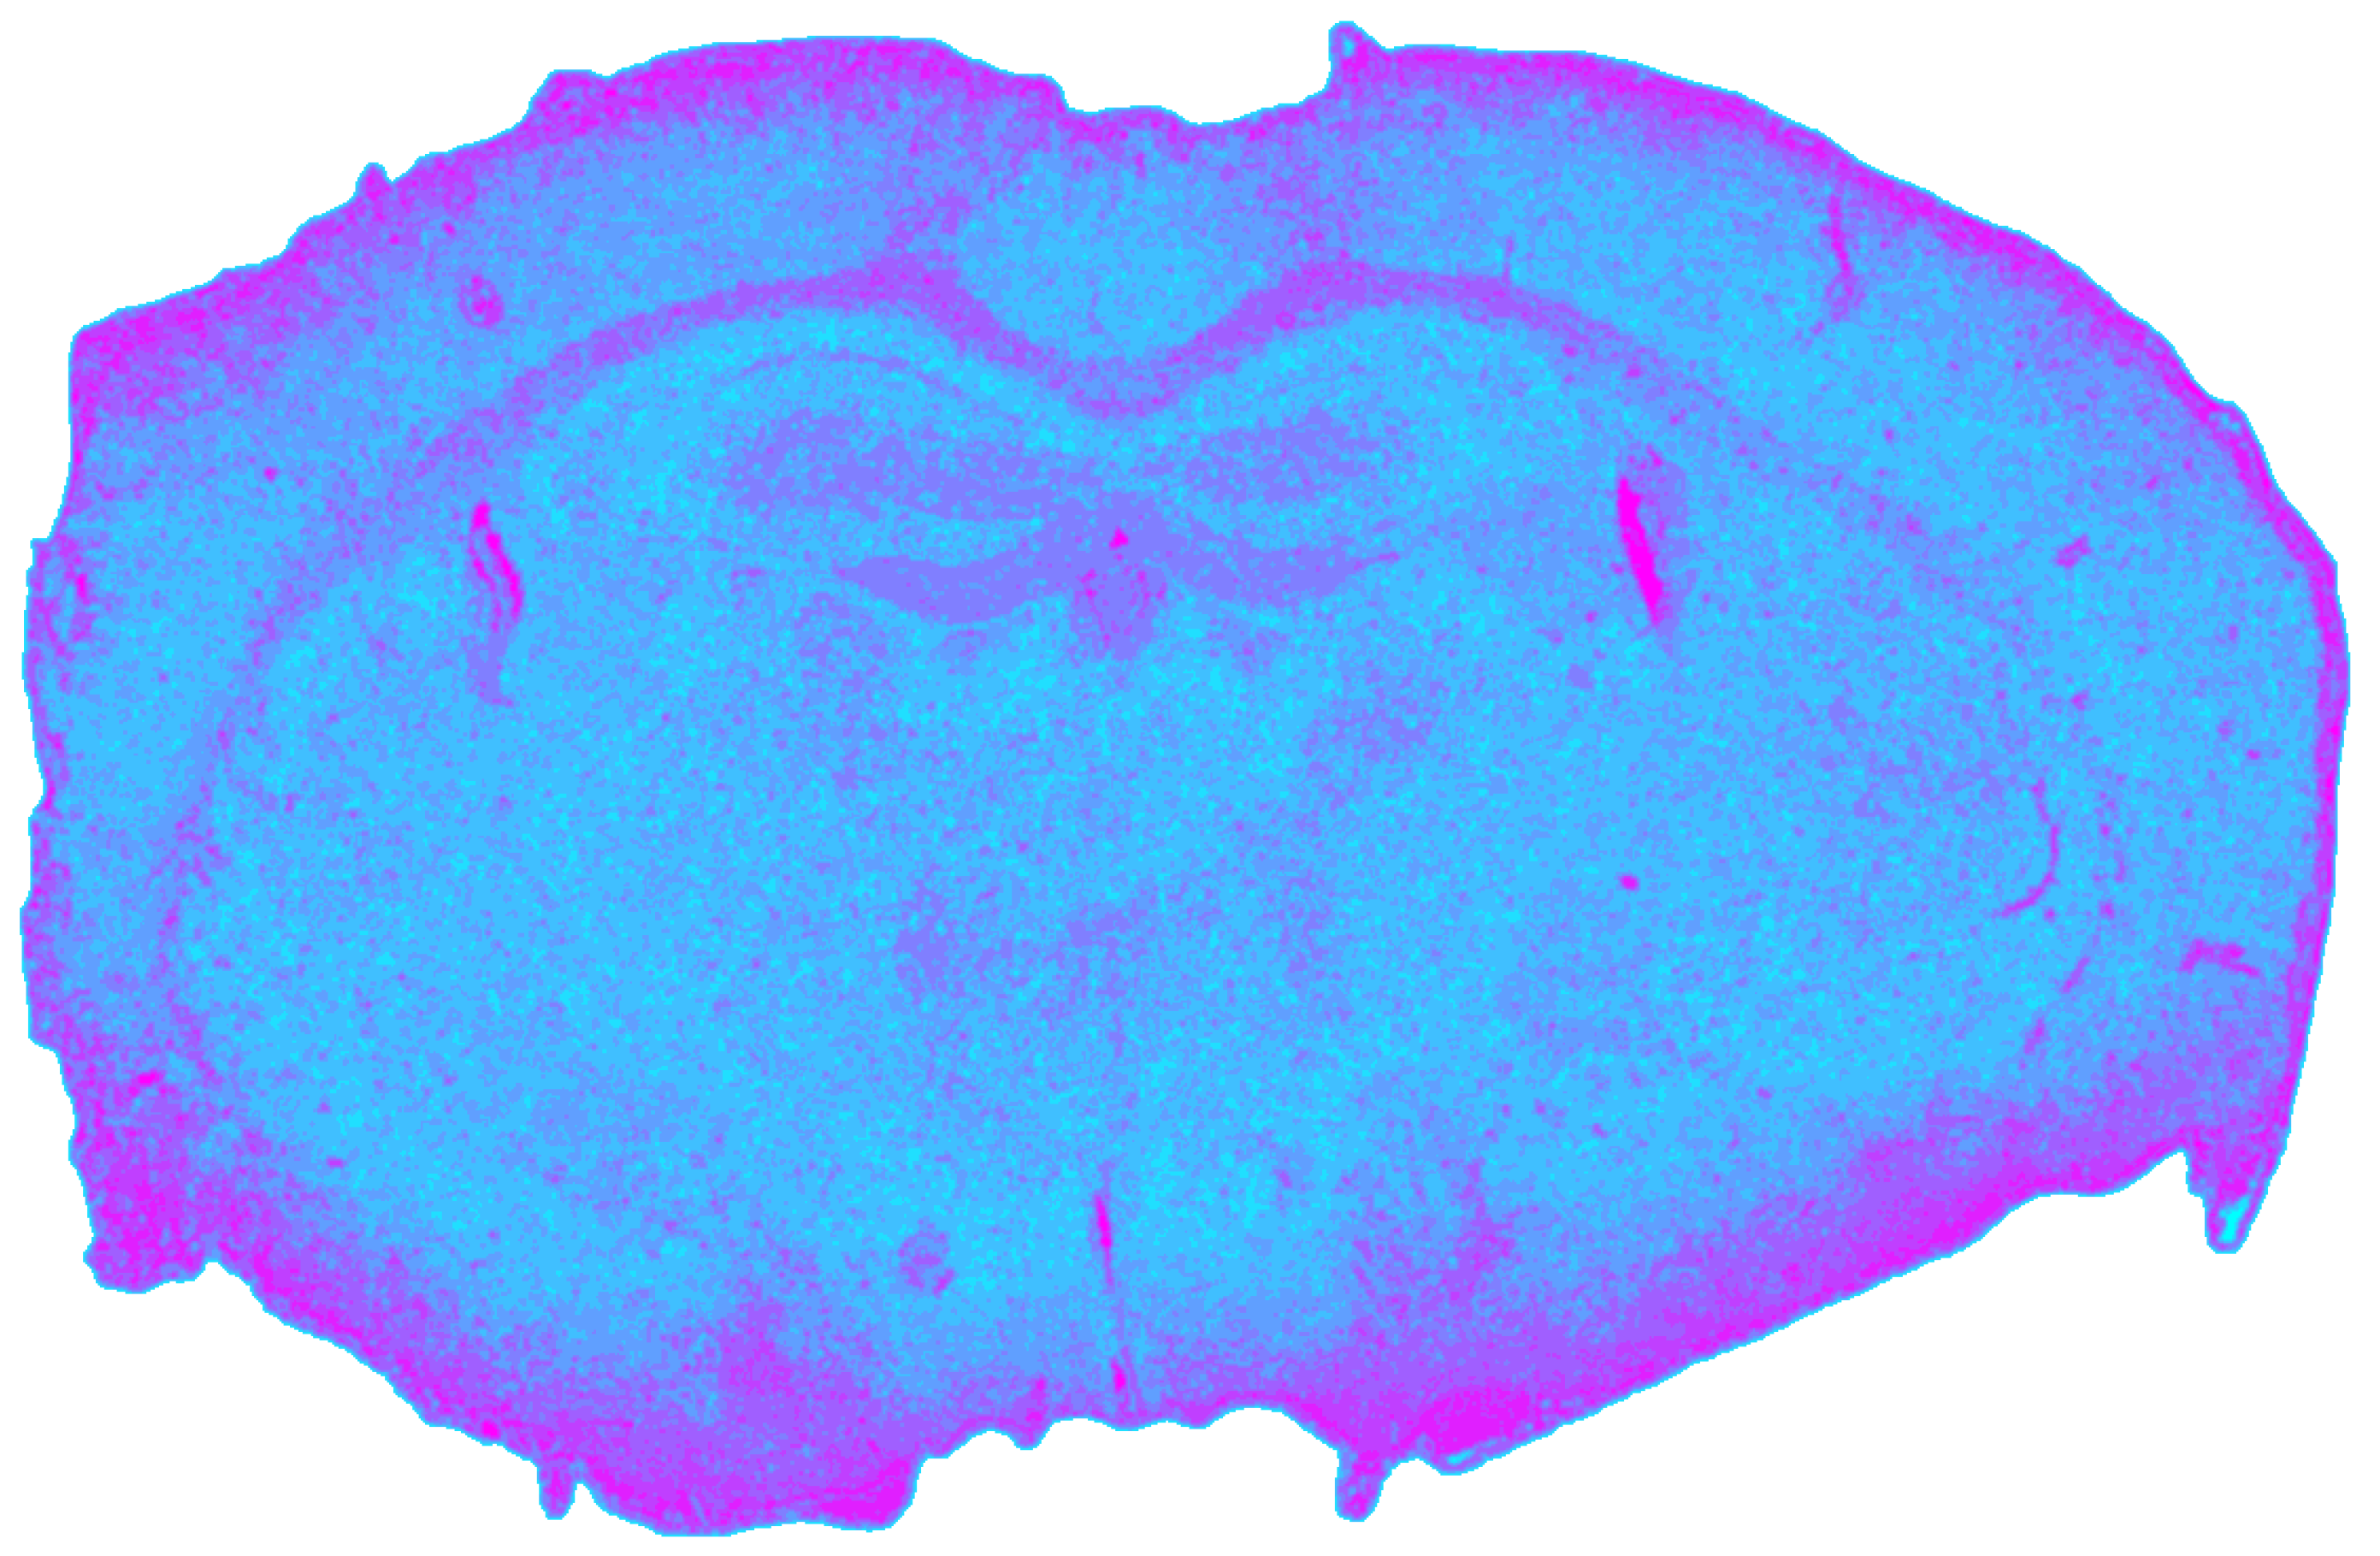

3.2. MIR Processing Results

Correcting the MIR dataset for vignetting and background prior to normalization yielded the most stable single-modality segmentation, with a silhouette coefficient of sMIR = 0.6020. Compared to NIR, MIR data exhibited sharper cluster boundaries and stronger spectral discrimination.

As shown in Figure 6, gray matter regions were more clearly separated than in NIR, while major white matter tracts were consistently resolved as compact clusters. MIR imaging also provided the strongest contrast for CSF compartments, both the ventriculus lateralis and ventriculus tertius formed distinct clusters. As depicted in Table 3, this improved separability in the MIR domain reflects the dominance of lipid-associated CH2/CH3 stretching bands in white matter, stronger amide I/II and phosphate-related absorptions in gray matter, and water-dominated spectra in CSF, which together enhance interclass spectral contrast compared to the NIR range.

Figure 6. Spatial clustering map of the preprocessed MIR datacube obtained with Mini-Batch KMeans (k = 9), showing the unsupervised segmentation of the mouse brain section into spectral tissue classes. Colors are consistent across figures and represent categorical cluster labels.